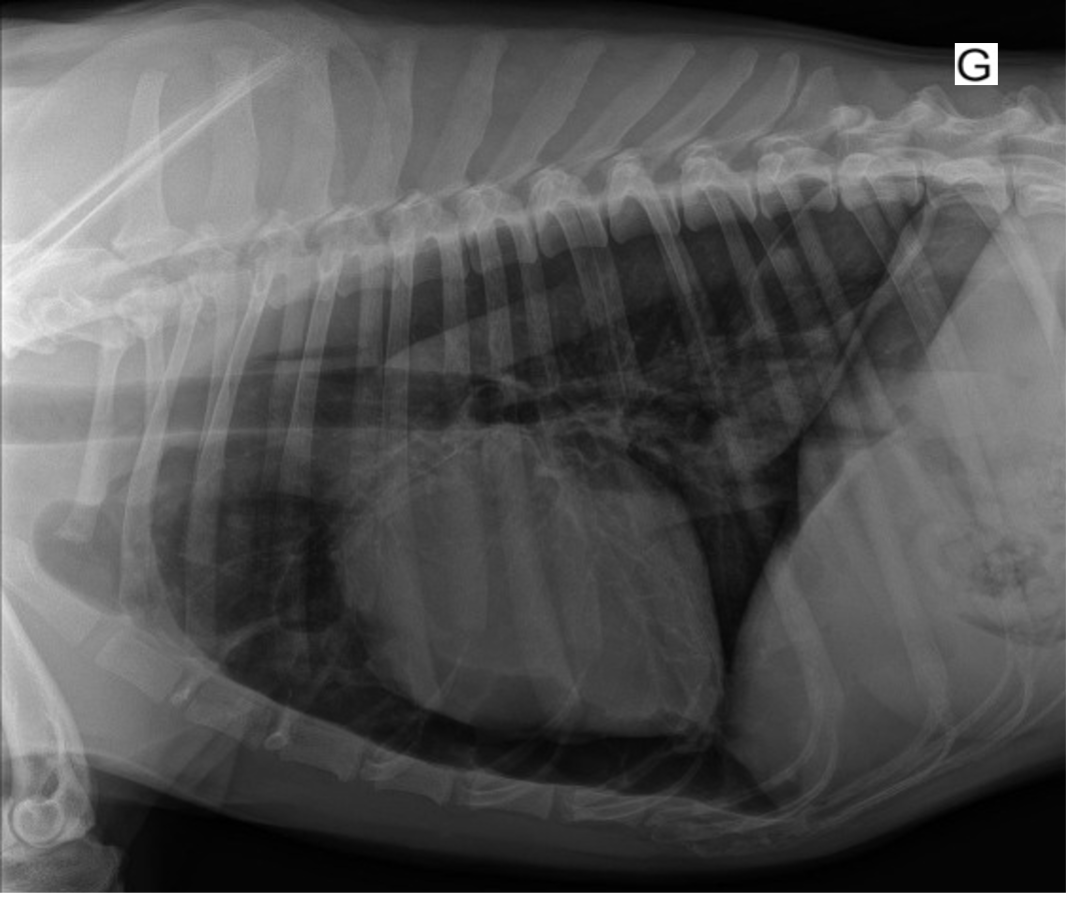

Il est décidé de réaliser une approche conservatrice. Un rendez-vous de contrôle est fixé 15 jours après l’accident. La chienne est en bon état général et sa fréquence respiratoire est dans les normes de l’espèce. Des radiographies thoraciques sont réalisées et montrent une normalisation des images avec disparition des pseudokystes (figures 7 et 8).

Figure 7 : Radiographie du thorax lors du contrôle, vue de profil droit.